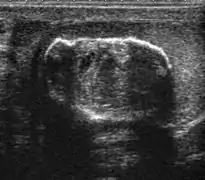

Teratoma Although teratoma is the second most common testicular tumor in children, it affects all age groups. Mature teratoma in children is often benign, but teratoma in adults, regardless of age, should be considered malignant. Teratomas are composed of all three germ cell layers, i.e. endoderm, mesoderm and ectoderm. At ultrasound, teratomas generally form well-circumscribed complex masses. Echogenic foci representing calcification, cartilage, immature bone and fibrosis are commonly seen [Fig. 5]. Cysts are also a common feature and depending on the contents of the cysts i.e. serous, mucoid or keratinous fluid, it may present as anechoic or complex structure [Fig. 6].

Fig. 5. Teratoma. A plaque-like calcification with acoustic shadow is seen in the testis.